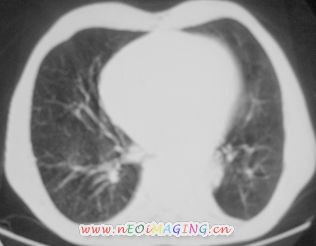

以下是引用卜一在2007-10-7 9:38:00的发言:[br]左下肺胸膜下团片影,内见含气支气管像,临近胸膜未见增厚。多考虑:1 左下肺炎症,建议消炎后复查!2 不除外肺隔离症合并感染!